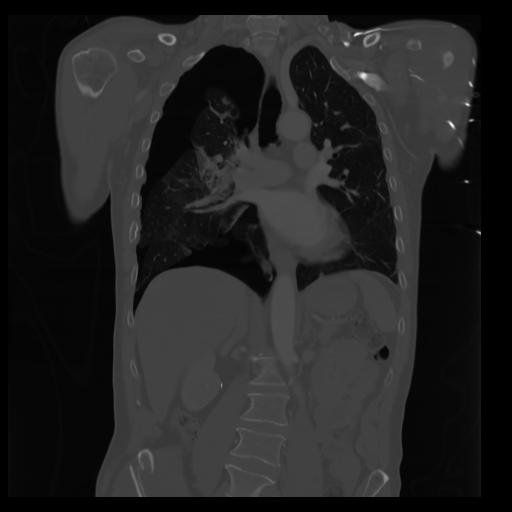

29 CUERPO,CE,Coronal,3.000,CUERPO,Coronal,